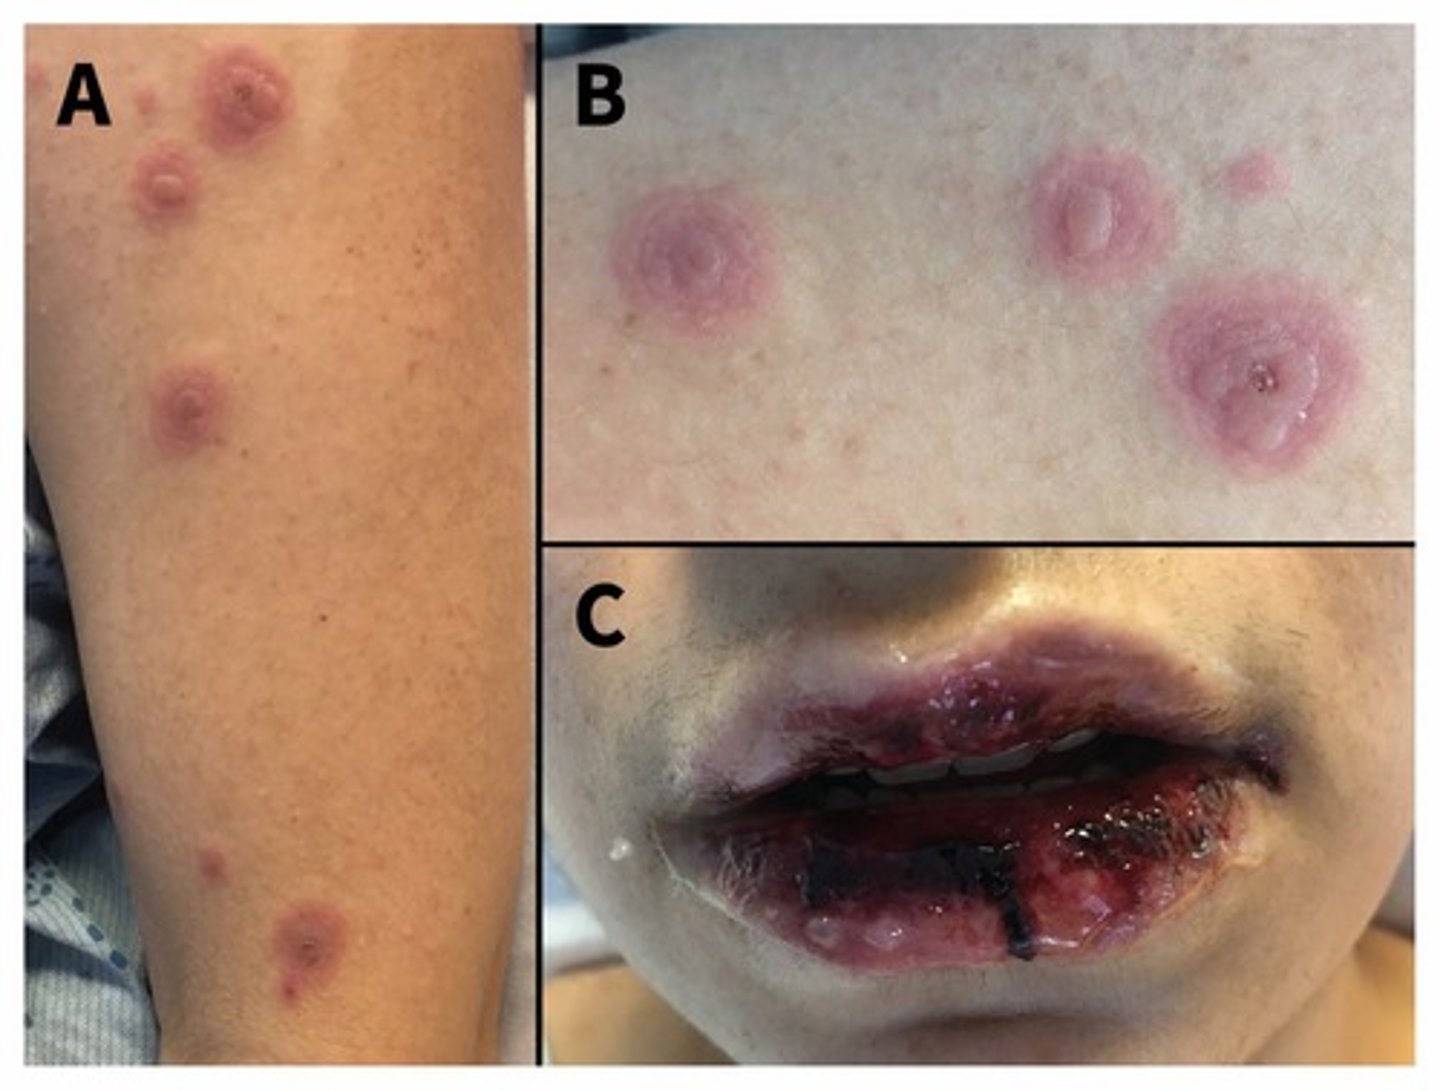

3. Mycoplasma infection has characteristic skin features - target lesions. This can give you inflammation of mucous membranes. There tends to be a long pre illness that doesn't show respiratory symptoms.